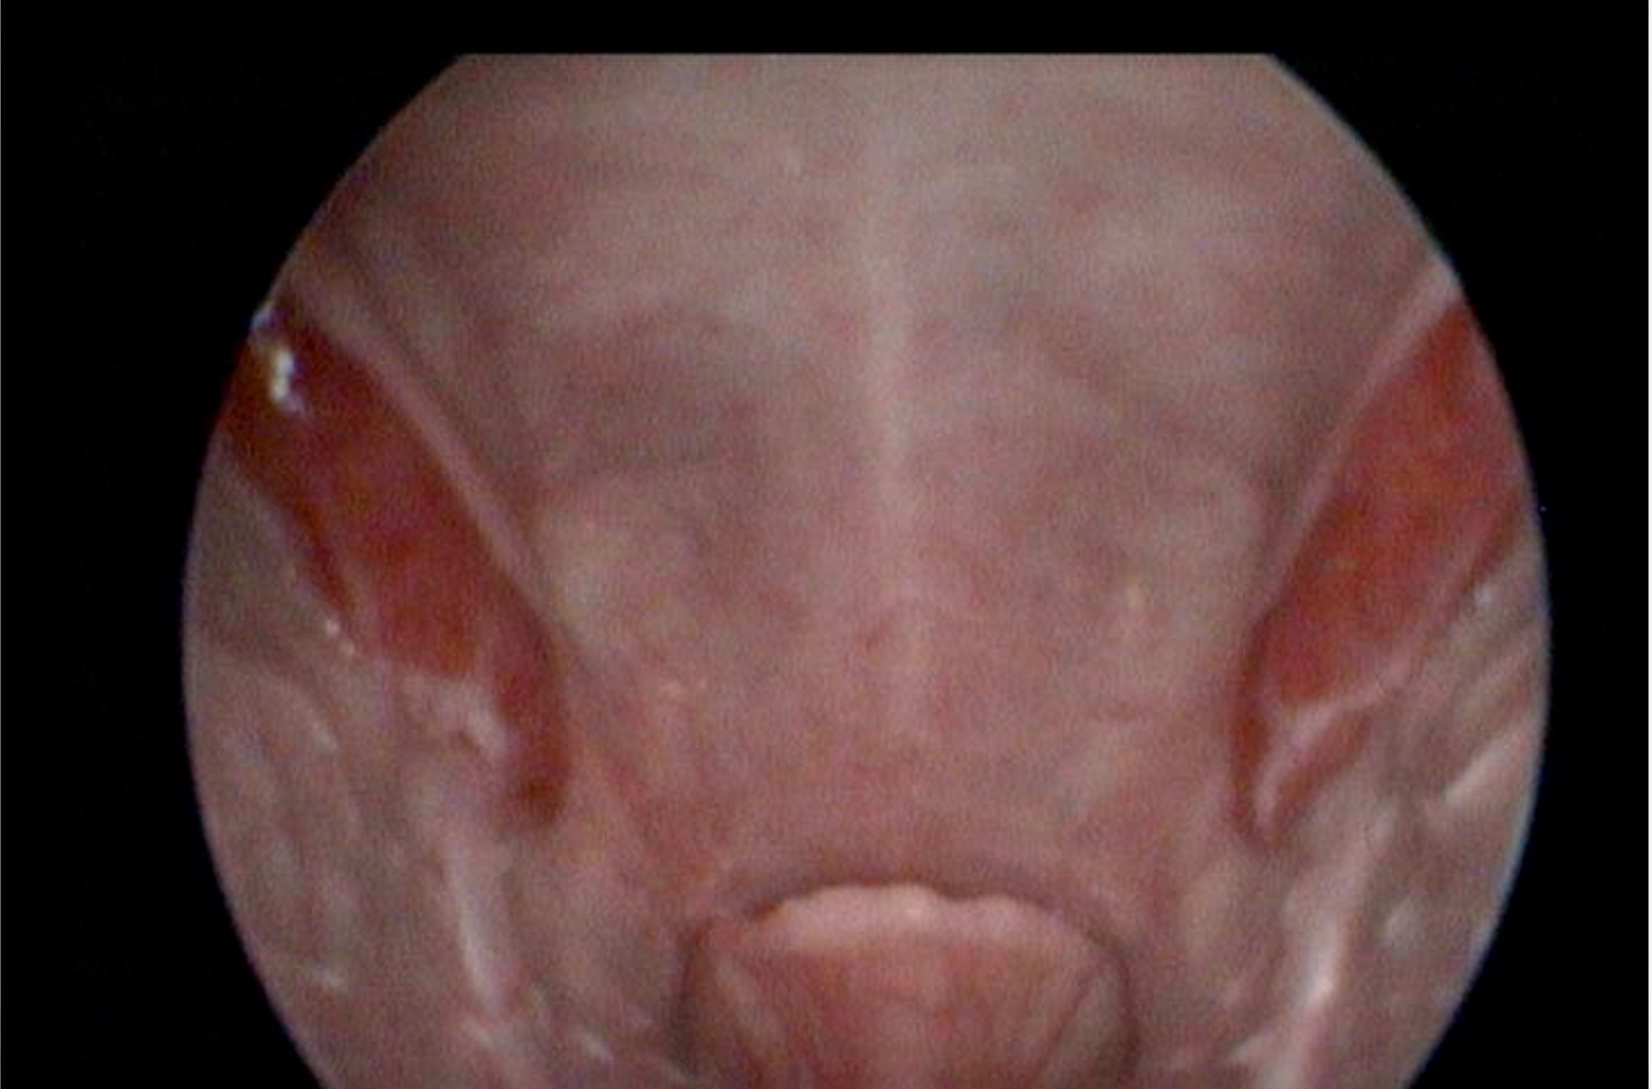

meine Huskyhündin hat heute die Verdachtsdiagnose GERD bekommen. Die Beschwerden fingen schon im Welpenalter an (sie ist jetzt 8 Jahre alt). In den ersten Jahren war es immer nur ein Husten und Würgen nach dem Trinken, so dass ich immer dachte, sie wäre zu schnell dabei und würde sich Verschlucken 🙈. Hinzu kam dann nach kurzer Zeit ein immer wieder auftretender Schluckauf, der auch bis heute besteht. Als sich die Beschwerden im Laufe der Jahre verschlechtert haben, wurde zunächst vom Tierarzt auf die Schilddrüse getippt, was aber mit einem großen Schilddrüsen-Profil (8 Werte) ausgeschlossen werden konnte. Da sich die Beschwerden in den letzten Monaten verschlimmert haben, wurde zunächst für 1/2 Jahr mit Verdacht auf auf Reflux mit GastroCalm und Slippery Elm behandelt, was aber auch keine wirklich durchgreifende Wirkung zeigte. Zum Ausschluss einer partiellen Larynxlähmung wurde dann heute eine Endoskopie durchgeführt. Diese wurde zar nicht bestätigt, aber der Bereich ist entzündlich, vor allem die Mandeln und der Nasenboden sind stark gerötet.